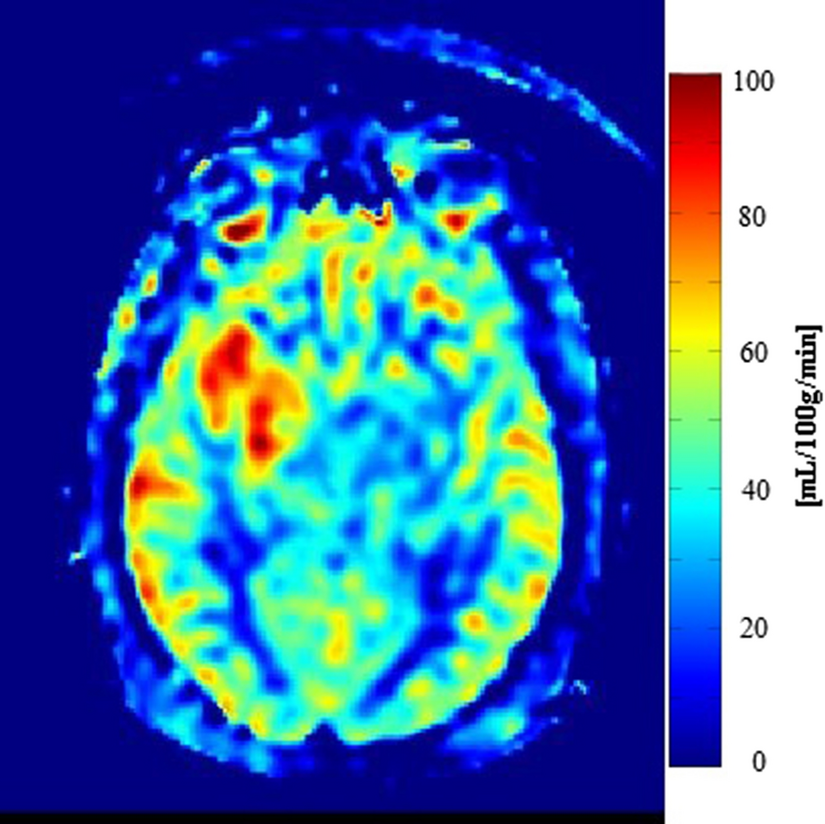

An alternative parameter to assess vascular proliferation within glioblastoma is regional cerebral blood flow (CBF). Relative CBF has shown a positive correlation with rCBV and microvascular density as an increase in CBF can be observed in high-grade gliomas; see Fig. 5 [51, 52]. Arterial spin labelling (ASL) is a non-invasive MR technique used to measure CBF and was found useful for non-invasive glioma grading [53]. By magnetically labelling the water molecules in arterial blood, which then flows into the brain, a tagged image of the brain can be acquired. Subtraction between labeled and control images creates images with signal weighted by cerebral perfusion that via a kinetic model can be quantified to generate images of CBF [54].

Fig. 5

ASL-CBF shows increased perfusion in a patient with a glioblastoma in the right frontotemporal lobe